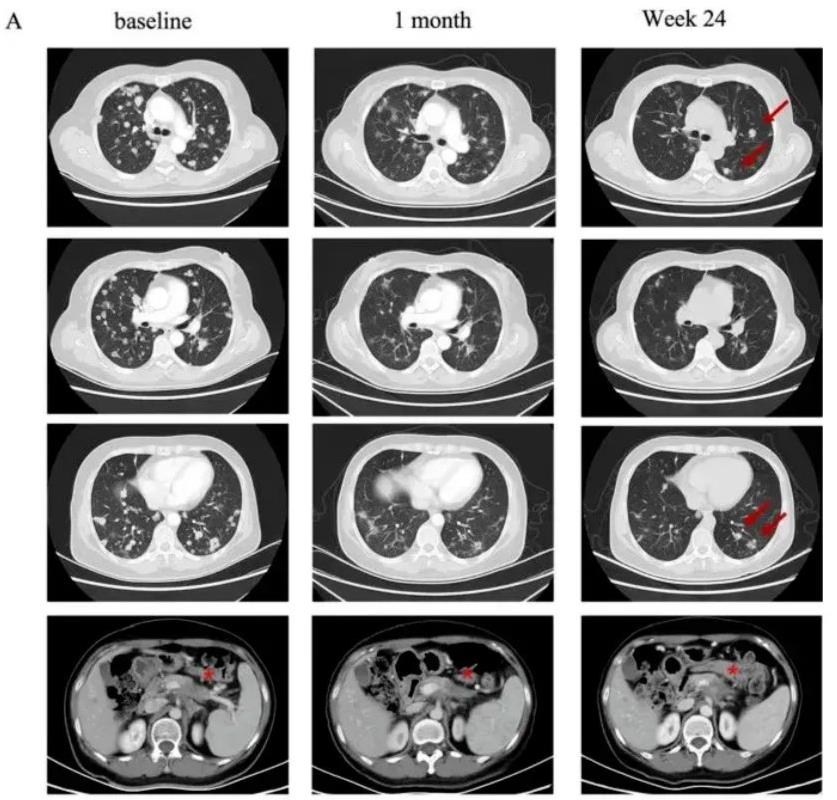

世界知名期刊《血液学与肿瘤学杂志》上,曾报道过“CT041治疗转移性胰腺癌后,肿瘤病灶显著缩小”的案例。本例患者为一名58岁的女性,确诊为转移性胰腺癌,既往曾接受过多种标准治疗,但效果不佳,肿瘤持续进展,且已发生全身转移,此时临床再无适合她的其他方法。抱着最后一丝希望,她入组了CT041(我国自主研制的一款针对Claudin18.2的新型CAR-T细胞产品)的临床试验。

令所有人惊喜的是,该患者在接受CT041治疗后,奇迹般地获得了部分缓解(PR),不仅靶病灶显著缩小超过30%,而且肺转移灶竟然也出现了大幅度缩小(详见下图)!

图2 该患者在CT041治疗前后,肺部影像学对比

▲图源“Penn Medicine News”,版权归原作者所有,如无意中侵犯了知识产权,请联系我们删除

注:“★”表示“原发病变”